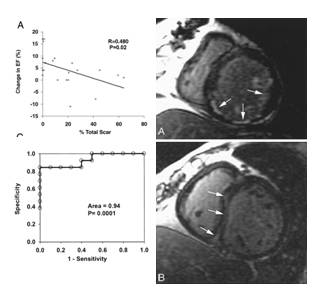

DE-CMR预测CRT无反应

◆入选28例CRT植入患者

◆应用DE-CMR评价心肌瘢痕

◆CRT无反应组中瘢痕负荷显著高于有反应组

◆瘢痕负荷和临床、超声指标改善程度呈反比

◆DE-CMR中瘢痕负荷>15%预测CRT无反应的灵敏度为85%,特异度为90%